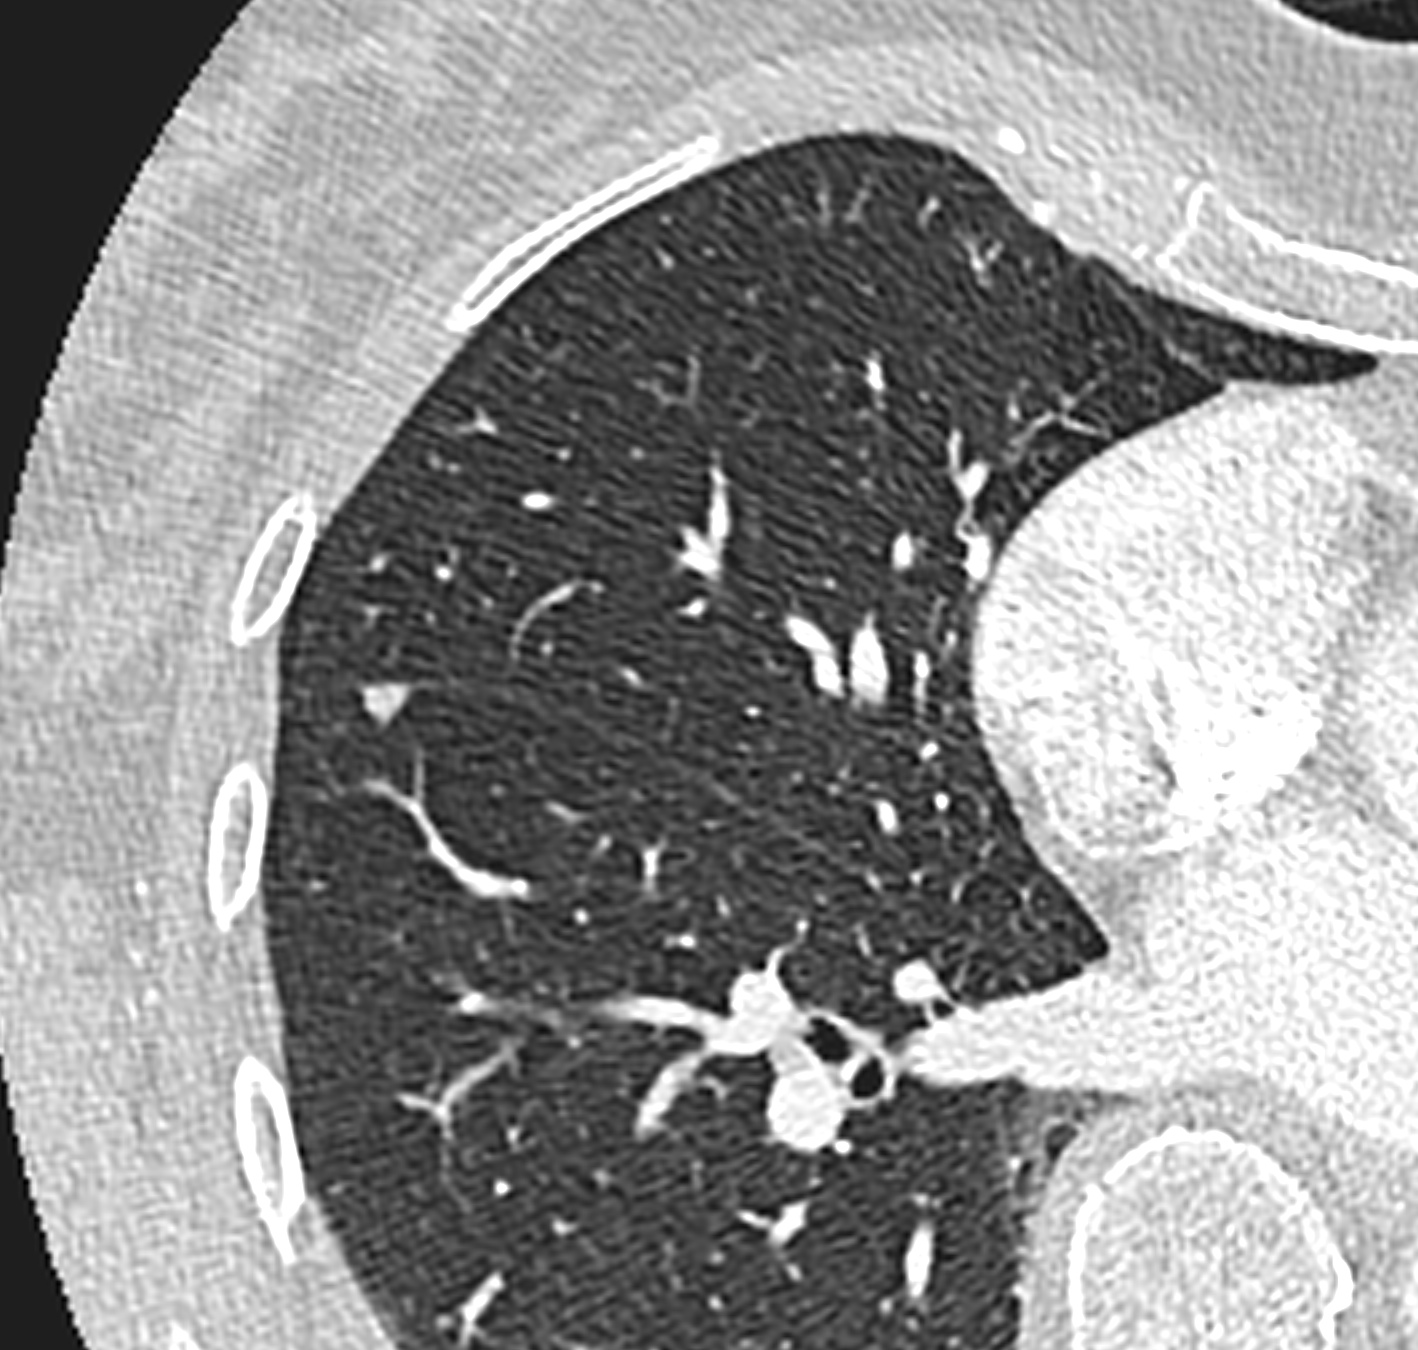

Il nodulo polmonare è un’opacità di dimensione < 3 cm, che non coinvolge la pleura, ed in genere non è associato a linfoadenopatia.

Per valutare il nodulo polmonare, vengono descritti dimensione, velocità di crescita ed alcuni aspetti morfologici :

• Densità. Può essere solida, a vetro smerigliato o parzialmente solida

• Forma. Nella maggior parte dei casi è rotonda o ovalare, ma può essere anche triangolare o poligonale (come spesso nel caso di linfonodi periscissurali), spiculati o stellati

• Margini. Possono essere lisci, lobulati o spiculati

• Contenuto. In caso di presenza di tessuto adiposo, calcificazioni o cavitazioni.

• Sono utili all’inquadramento del nodulo polmonare anche altri reperti come: retrazione pleurica, segno del broncogramma aereo, pseudocavitazioni, pattern cistico (raro) ed il vascular convergence sign.